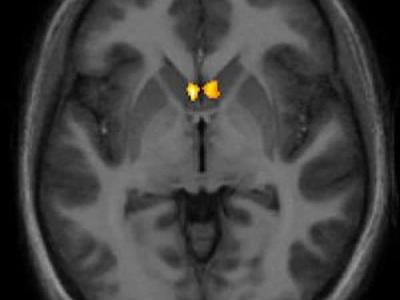

研究发现爱情有助缓解疼痛 美国科学家最新研究发现,爱情有助缓解疼痛,可能有助...